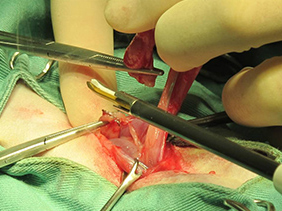

お腹に小さな穴を開けてとトロッカーを差込みます。

卵巣をつかみ超音波メスで切り取ります。